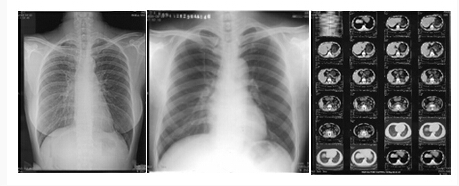

扫描样片